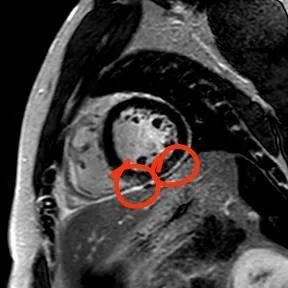

“快!做磁共振觀(guān)察心肌有無(wú)受損及程度?!庇跋裨\療中心陳寶瑩副主任為小燁進(jìn)行心臟磁共振平掃及增強(qiáng)掃描。結(jié)果提示:患者有急性心肌損傷,考慮心肌梗死。結(jié)果驗(yàn)證了小燁的心肌大片區(qū)失活。

方向比努力更重要,對(duì)于醫(yī)生而言更是如此,準(zhǔn)確把握病因方向,才能有效治療。心臟磁共振,成為非侵入性診斷心肌疾病的金標(biāo)準(zhǔn),能準(zhǔn)確地鑒別心肌炎、應(yīng)激性心肌病、心肌病淀粉樣變性、擴(kuò)張性心肌病及心肌梗死等,并能對(duì)心肌梗死后心肌纖維化進(jìn)行定量評(píng)估。